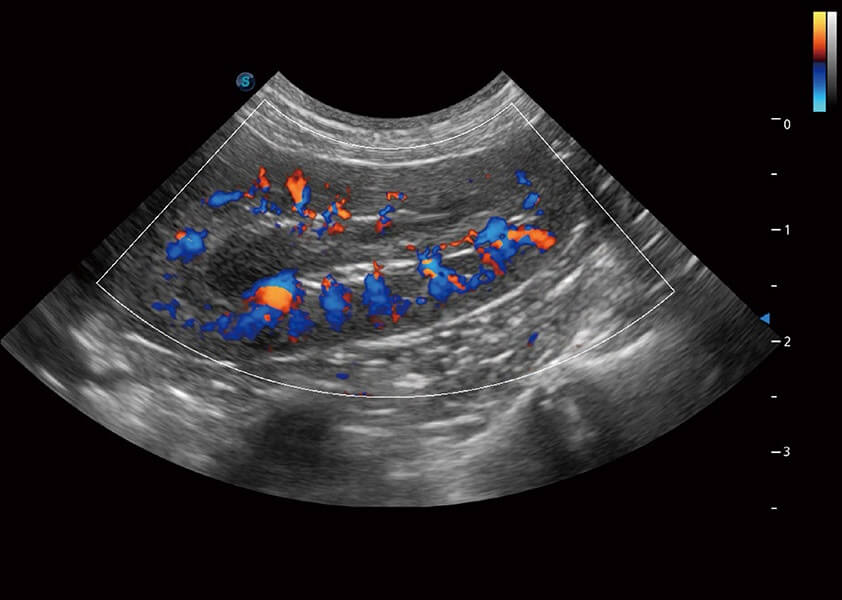

(犬)四腔心血流

(犬)肾脏血流